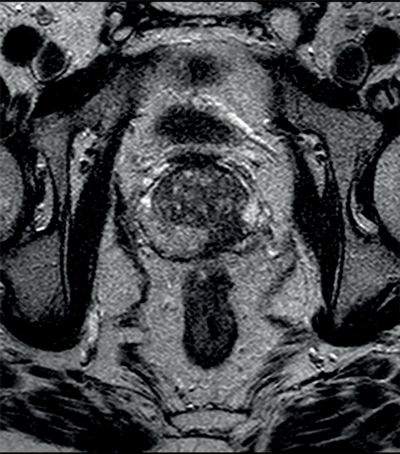

On conventional T2WI, peripheral zone prostate carcinomas appear as a low signal area within the normally high signal peripheral zone. However, as described above, many noncancerous pathologies may also appear as low signal within the peripheral zone, lowering the specificity of T2WI alone in detecting prostate cancer. DWI can aid diagnosis, as prostate carcinoma demonstrates restricted diffusion due to the replacement of normal glandular architecture with tightly packed tumour cells and fibrotic stroma, thereby restricting the movement of water molecules [1].

Tumours appear as high signal areas on DWI and low signal areas on ADC map (Figure 1).

Figure 1a: Axial T2WI showing low signal left peripheral zone tumour.

Figure 1b: DWI showing high signal at the site of tumour.

Figure 1c: ADC map with low signal seen confirming restricted diffusion.